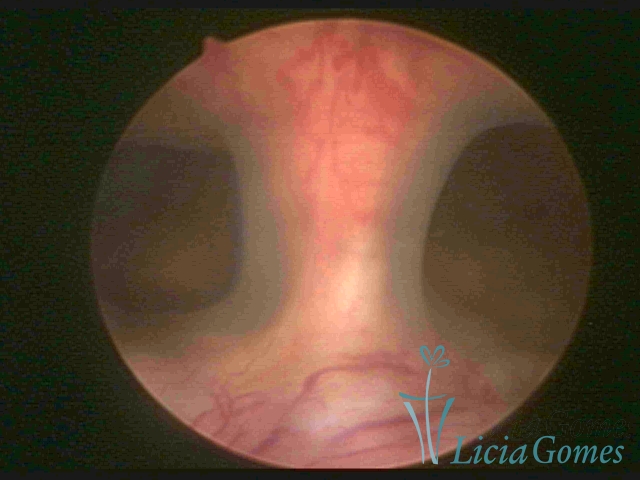

Uterus didelphys

The presence of two uterine cervices and a double vagina, similar to unicornuate uteri, with a normal covering of endometrium.